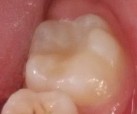

Bệnh nhân: Ng. Minh T. 9 tuổi. Răng 36, mã BA 13519/17

Sau ba tháng. ICDAS:2; Di: 22 | Sau 12 tháng. ICDAS:0; Di: 09 | Sau 18 tháng. ICDAS:0; Di: 05 |